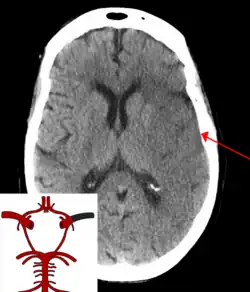

CT scan of the brain showing a massive, prior right-sided ischemic stroke from blockage of an artery. Changes on a CT may not be visible early on.[1]

The most significant risk factor for stroke is high blood pressure.[7] Other risk factors include high blood cholesterol, tobacco smoking, obesity, diabetes mellitus, a previous TIA, end-stage kidney disease, and atrial fibrillation.[2][7][8] Ischemic stroke is typically caused by blockage of a blood vessel, though there are also less common causes.[13][14][15] Hemorrhagic stroke is caused by either bleeding directly into the brain or into the space between the brain's membranes.[13][16] Bleeding may occur due to a ruptured brain aneurysm.[13] Diagnosis is typically based on a physical exam and supported by medical imaging such as a CT scan or MRI scan.[9] A CT scan can rule out bleeding, but may not necessarily rule out ischemia, which early on typically does not show up on a CT scan.[10] Other tests such as an electrocardiogram (ECG) and blood tests are done to determine risk factors and possible causes.[9] Low blood sugar may cause similar symptoms.[9]